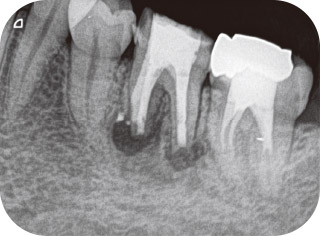

症例1-1 初診時X線写真。頰側歯肉の腫脹が消えないとのことで近医より紹介。歯髄の診断は歯髄処置済歯、根尖周囲組織の診断は症状のある根尖性歯周炎ならびに慢性根尖膿瘍と診断し、再根管治療の必要性を説明し、治療開始。 -

症例1-2 2回の治療で終了。根管充填時のX線写真。根管充填後も頰側歯肉の腫脹が消失しないため、根尖性歯周炎の問題解決には至っていないと判断し、歯根端切除術を行う。 -